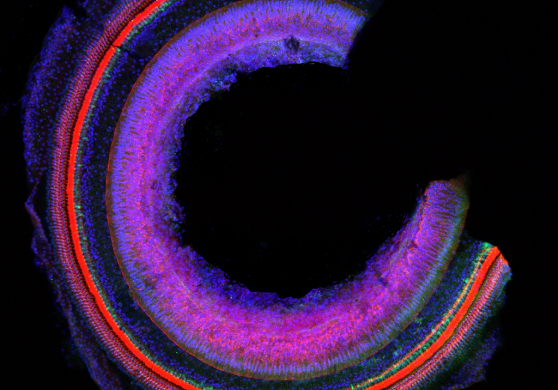

듣기를 담당하는 달팽이관은 소리의 주파수와 강도에 따라 아래 기저부에서

가장 끝인 첨단부까지 선택적으로 이를 자극하고 유모세포를 통해 소리를 감지한다.

달팽이관은 피아노의 건반처럼 각각의 영역이 소리의 특성을 대변하는 체계적인 구조를 갖추고 있어 이를 알아내고자 세계적으로 많은 연구가 진행 중이다. 연구진은 나선형의 달팽이관 속 기저막 위에 있는 코르티기관을 촬영해 청각의 신비로움을 표현했다.

Mystery of hearing

듣기를 담당하는 달팽이관은 소리의 주파수와 강도에 따라 아래 기저부에서 가장 끝인 첨단부까지 선택적으로 이를 자극하고 유모세포를 통해 소리를 감지한다. 달팽이관은 피아노의 건반처럼 각각의 영역이 소리의 특성을 대변하는 체계적인 구조를 갖추고 있어 이를 알아내고자 세계적으로 많은 연구가 진행 중이다. 연구진은 나선형의 달팽이관 속 기저막 위에 있는 코르티기관을 촬영해 청각의 신비로움을 표현했다.